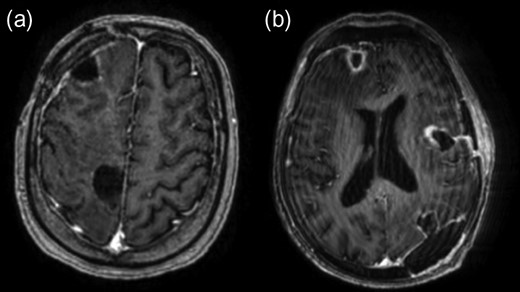

Commencement of dexamethasone (8 mg twice-daily) initially resulted in a good clinical response. Image-guided excision of the right frontal abscess was undertaken and culture results identified Nocardia farcinica. Despite appropriate treatment with intravenous linezolid combined with imipenem and the subsequent addition of co-trimoxazole, repeat imaging demonstrated a continued increase in size of the remaining abscesses. Two further operations were performed over a 4-week period in addition to ongoing anti-microbial therapy. Resection of all abscesses was achieved through right frontal, right parietal, left parieto-occipital and left temporal craniotomies. Microbiological analysis identified Enterococcus faecium in a second abscess and vancomycin was added to the antibiotic regimen. Post-operative imaging indicated complete resection and appearances were monitored with regular imaging (Fig. 2). A prolonged course of dexamethasone was required to maintain neurological function. This may have contributed to a wound dehiscence requiring an uneventful wash-out and repeat closure in theatre. Ongoing seizure activity was controlled with anticonvulsants.

Post-contrast axial T1-weighted MRI following resection of abscesses in the right frontal lobe (a, b), left insular region (b) and left occipital lobe (b).